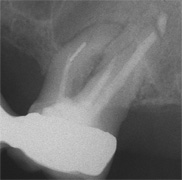

Der umfangreiche kariöse Defekt steuerte sehr bald hin auf die komplette Entfernung des Zahninnen­gewebes mit anschliessendem medikamentösen Wiederverschluss. Aufbissempfindlichkeit am Folgetermin ist immer Aufforderung zur erneuten Intensivsuche nach weiteren Kanälen, die hier einen 4. Ast zum Vorschein brachte. Nach 2 ausgelassenen Terminen

waren vorrangig Wiederherstellung von desinfizierender Einlage und provisorischer Füllung angezeigt. Eine weitere Woche später wurde in allen Kanälen das Medikament durch die endgültige Verschlussmasse ersetzt, worauf Zahn 36 mit 12-tägiger Verzögerung erneut zu rebellieren begann. Das hiess aus den hinteren Wurzeln Füllmaterial wieder raus und

Einlage erneut rein. Als es dann 4 Wochen später bei der hinteren Wur­zel aussen anzuschwellen begann und ein Medikamentenwechsel ohne Wir­kung blieb, wurden die hinteren Ka­näle abgefüllt und auch in gleicher Sitzung das überstopfte Material (Bild 1) mittels Resektion (Bild 2) von aussen entfernt.

Die ersten beiden Aufnahmen sind aus dem Jahr 1999, die 3. von 2006